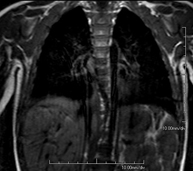

- Chest MRI

This non-invasive diagnostic procedure uses an electromagnetic field and radio waves (from a transmitter and receiver) to acquire high-definition anatomical images of the chest. It is a radiation-free procedure. It is indicated for lung lesions in which infiltration of the mediastinum or thoracic wall must be ruled out, to differentiate between solid and cystic chest lesions, etc. Sometimes paramagnetic contrast (gadolinium) must be used to complete the study.